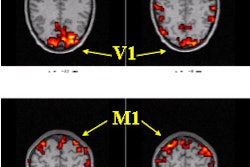

PML is caused by the Papova virus, which destroys the brain's oligodendrocytes, and causes a breakdown of myelin. It a progressive lesion, but dementia is uncommon. The lesions are typically seen in the occipital lobes. They are asymmetrical, and do not enhance with the administration of contrast in MRI. Patients with PML often die within six months of diagnosis, Corr said.